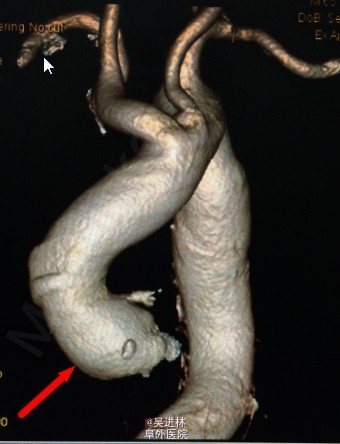

患者男,68岁,因“发现主动脉关闭不全11年”入院。患者11年前因头晕,就诊与当地医院,心脏超声提示:主动脉瓣关闭不全。后患者逐年复查,未行特殊治疗。1周前患者来我院就诊,超声提示:二叶瓣畸形,主动脉瓣重度狭窄办重度关闭不全,主动脉窦部及生主动脉增宽,未行手术入院。

诊断: 主动脉瓣二叶瓣畸形 主动脉关闭不全 主动脉窦部及生主动脉增宽 心脏扩大 心功II级 高血压病2级(极高危) 处理:手术换瓣bental

正常的主动脉瓣共有三个瓣膜。心脏收缩时,三个瓣膜同时打开,血液由左心室进入主动脉;心脏舒张时,三个瓣膜协同关闭,防止血液从主动脉返流入左心室。若主动脉瓣先天性只有两个瓣膜,称为主动脉瓣二瓣化畸形,是最常见的先天性主动脉瓣狭窄畸形。由于瓣叶结构异常,长期受到血流的不断冲击,易引起瓣膜增厚、钙化、僵硬、纤维化,最终导致瓣膜狭窄。这样会引起体循环灌注不足,头晕,乏力,心绞痛。更关键的,由于血流动力学改变,常常导致主动脉根部瘤样扩张。